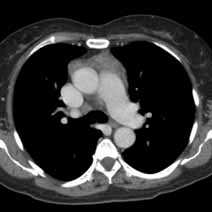

При проведении компьютерной томографии оценивают наличие вилочковой железы и положение в средостении: уровень и отношение к срединной линии, ее форму, линейные размеры, однородность структуры, четкость контуров, измеряют плотность нативно, а также в артериальную, венозную и отсроченную стадии. Аксиальные изображения КТ и комбинированные мультиплоскостные реконструкции могут быть использованы, чтобы идентифицировать инвазию опухоли в крупные кровеносные сосуды, перикард и легочную ткань. Если, опухоль имеет гладкие, четкие границы, однородную плотность, отсутствуют некрозы или кистозные изменения, видна жировая прослойка между опухолью и смежными структурами новообразование можно считать неинвазивным. Если, опухолевое новообразование имеет дольчатую или неправильную форму, нечеткие контуры, неоднородное усиление после внутривенного контрастирования, явное прорастание перикарда, легочной ткани, грудной стенки такую опухоль необходимо считать инвазивной.

Дифференциальная диагностика между гиперплазией и тимомой (рис.3-7) небольших размеров заключается в выявлении новообразования, локально выходящего за контур железы накапливающего контрастное вещество в разные фазы контрастирования отлично от неопухолевой ткани вилочковой железы.

КТ более точен в диагностике тимомы с ее повышенной чувствительностью при выявлении новообразований средостения, по сравнению с рентгенографией грудной клетки. Одна из важных, хотя и сложных задач КТ - определение местной инвазивности опухоли.

Хотя, как правило для идентификации образований тимуса контраст не требуется тем не менее его применение необходимо при локально инвазивных опухолях, когда оценка сосудистого кровотока позволяет выработать тактику операции и лечения.